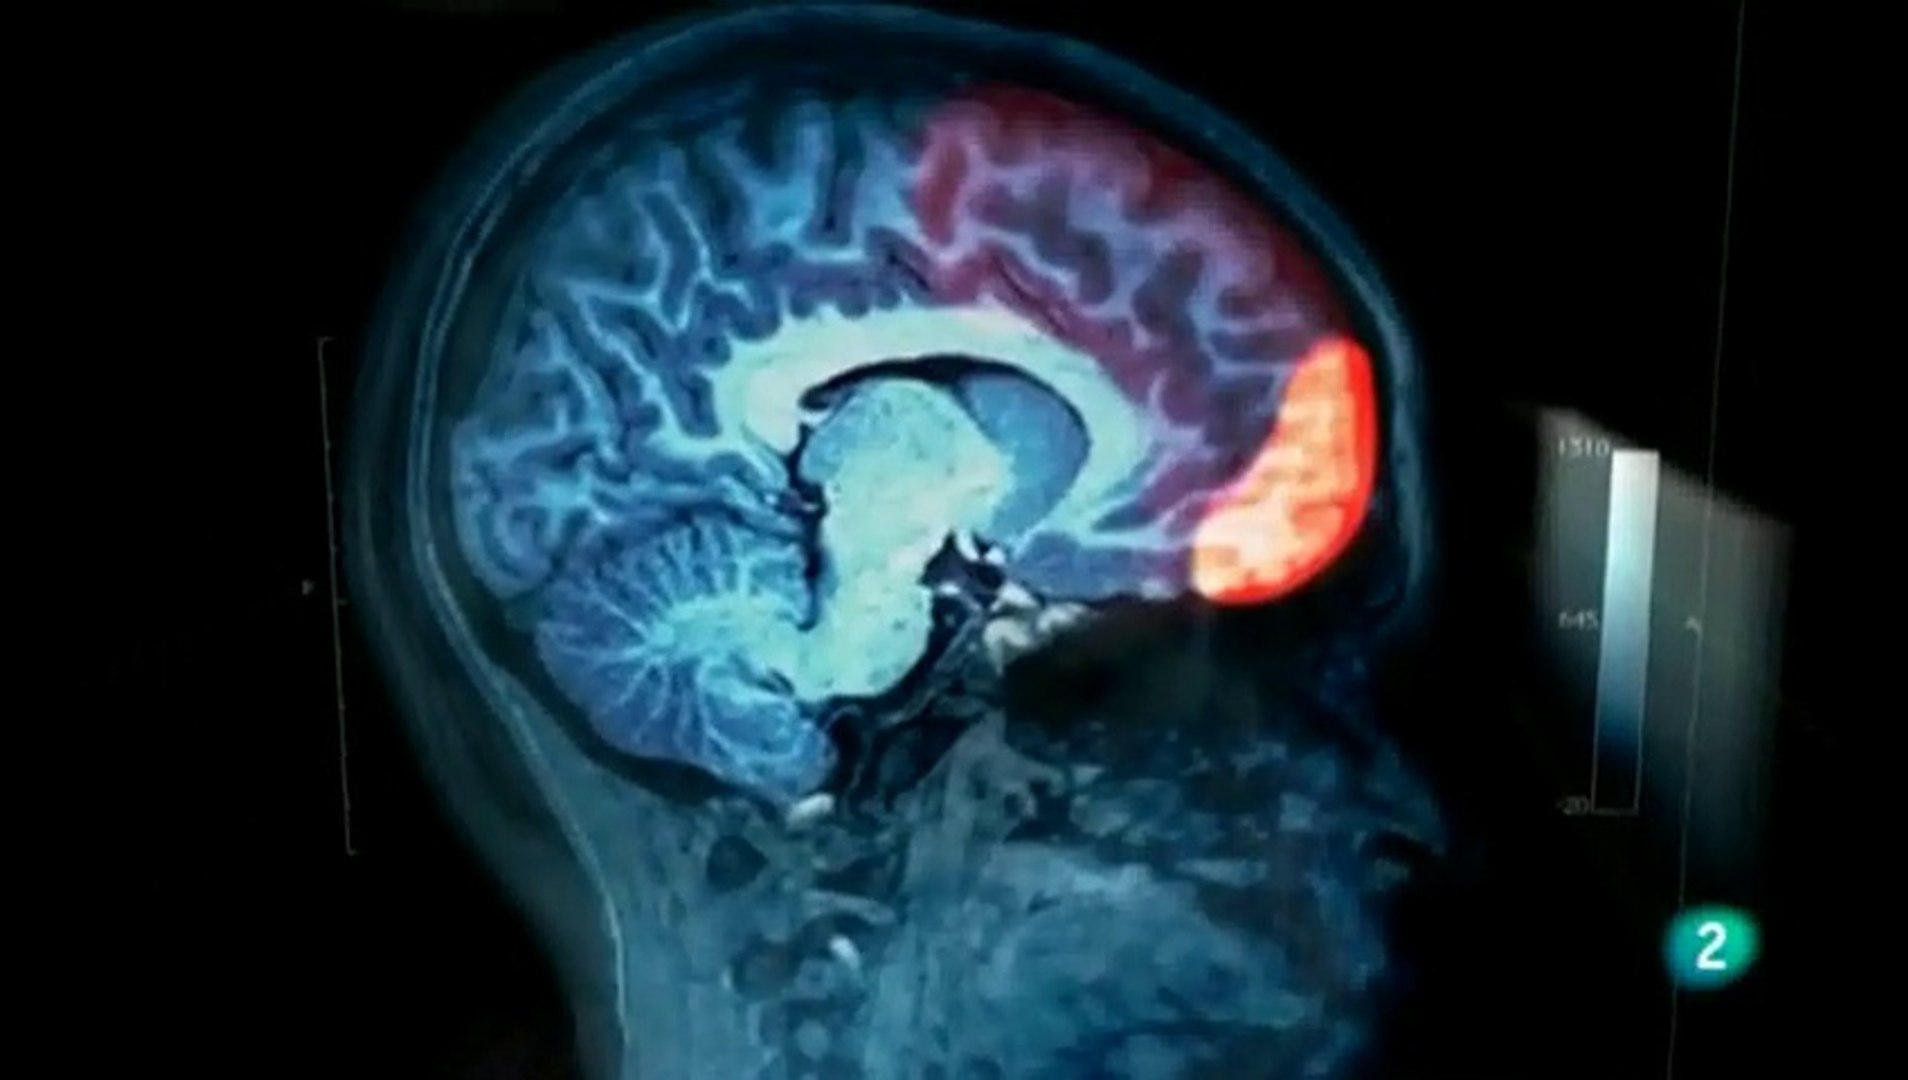

Un estudio está usando imágenes de resonancia magnética funcional (irmf) para mostrar cómo las anormalidades en áreas particulares del cerebro causan cambios en la función cerebral que producen síntomas de. Em 1981, a psiquiatra norte americana l. El documental trata de explicar cómo se comporta el cerebro de una persona con síndrome de asperger, para ello recurre a hugo, un personaje ficticio al que. Pueden ser la primera vez que un niño comienza a interactuar con otros niños. Sindrome de asperger en adultos los adultos con sindrome de asperger tienen problemas para demostrar empatía por los demás y las interacciones sociales siguen siendo difíciles.

El síndrome de asperger fue identificado en el año 1944 por un pediatra austriaco, hans asperger. Síndrome de asperger en los primeros años. Un estudio está usando imágenes de resonancia magnética funcional (irmf) para mostrar cómo las anormalidades en áreas particulares del cerebro causan cambios en la función cerebral que producen síntomas de. El síndrome de asperger (as por su abreviación en inglés) es un trastorno del desarrollo que lleva asociada una alteración neurobiológica, manifestando un conjunto de características mentales y de conducta que forma parte de los trastornos del espectro autista. Es caracteritza per presentar dificultats socials, interessos restrictius i conductes perseverants. El síndrome de asperger es uno de los trastornos del espectro autista (tea). El documental trata de explicar cómo se comporta el cerebro de una persona con síndrome de asperger, para ello recurre a hugo, un personaje ficticio al que. Dentro del amplio espectro que abarca el autismo hay un segmento de personas que sufren el trastorno que, al contrario 3 para una persona con síndrome de asperger el mundo es muy raro. Estos factores pueden llevar a los cambios en el revelado del cerebro que se convierte en el síndrome de asperger. Importantes consejos manual para comprender y aprender sobre este sindrome. Tal como ocurre con otros trastornos del espectro autista, los científicos no saben exactamente qué causa el síndrome de asperger, pero se conoce que el cerebro de alguien con esta afección funciona de forma diferente al. A pesar de que el síndrome de asperger es mucho más común que otros tipos de autismos, sigue siendo una condición rara y pocas personas, incluyendo profesionales, saben sobre ella y mucho menos tienen experiencia contrastada. (vale para todo el espectro autista, pero en autismo hemisf.